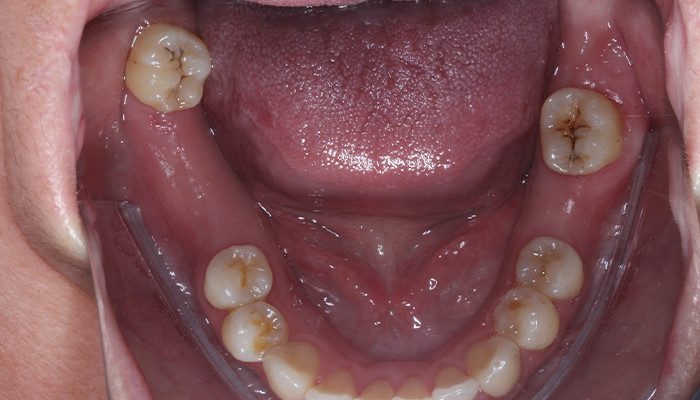

2 e 3 | Aspecto inicial intraoral.